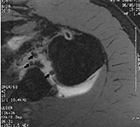

Mercury in the chest Mercury in the elbow Candy Shoulder MRI metallic artifacts

Axial three-dimensional MR arthrogram of the left shoulder in a 40 year-old man as follow-up from prior rotator cuff repair. The arrows point to areas of susceptibility (blooming) artifact from presumed tiny metallic deposits in the shoulder from the surgery. Shoulder radiographs were normal. From Hunter, 2003. Permission granted for use of images in this article by Radiological Society of North America (RSNA)